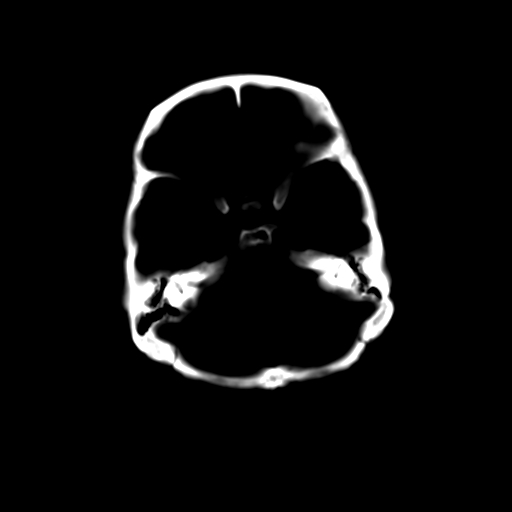

女,42岁,前额部外伤1小时,伤后头痛。

头颅ct平扫未见异常

未见明显异常!

颅脑ct平扫未见异常,必要时复查

颅内未见明显异常,枕骨松质骨瘤可能性大。颅骨板障起源骨瘤较常见,骨血管瘤有垂直骨针及粗大钙化,嗜酸性肉芽肿软组织有改变,典型者可见“纽扣状”死骨,年龄通常较小。

枕骨松质骨良性病变。

未见明显外伤性改变。

左枕骨松质骨不均匀低密度灶,边缘清楚,考虑良性松质骨性骨瘤可能性大。

不排除左枕骨嗜酸性肉芽肿可能。